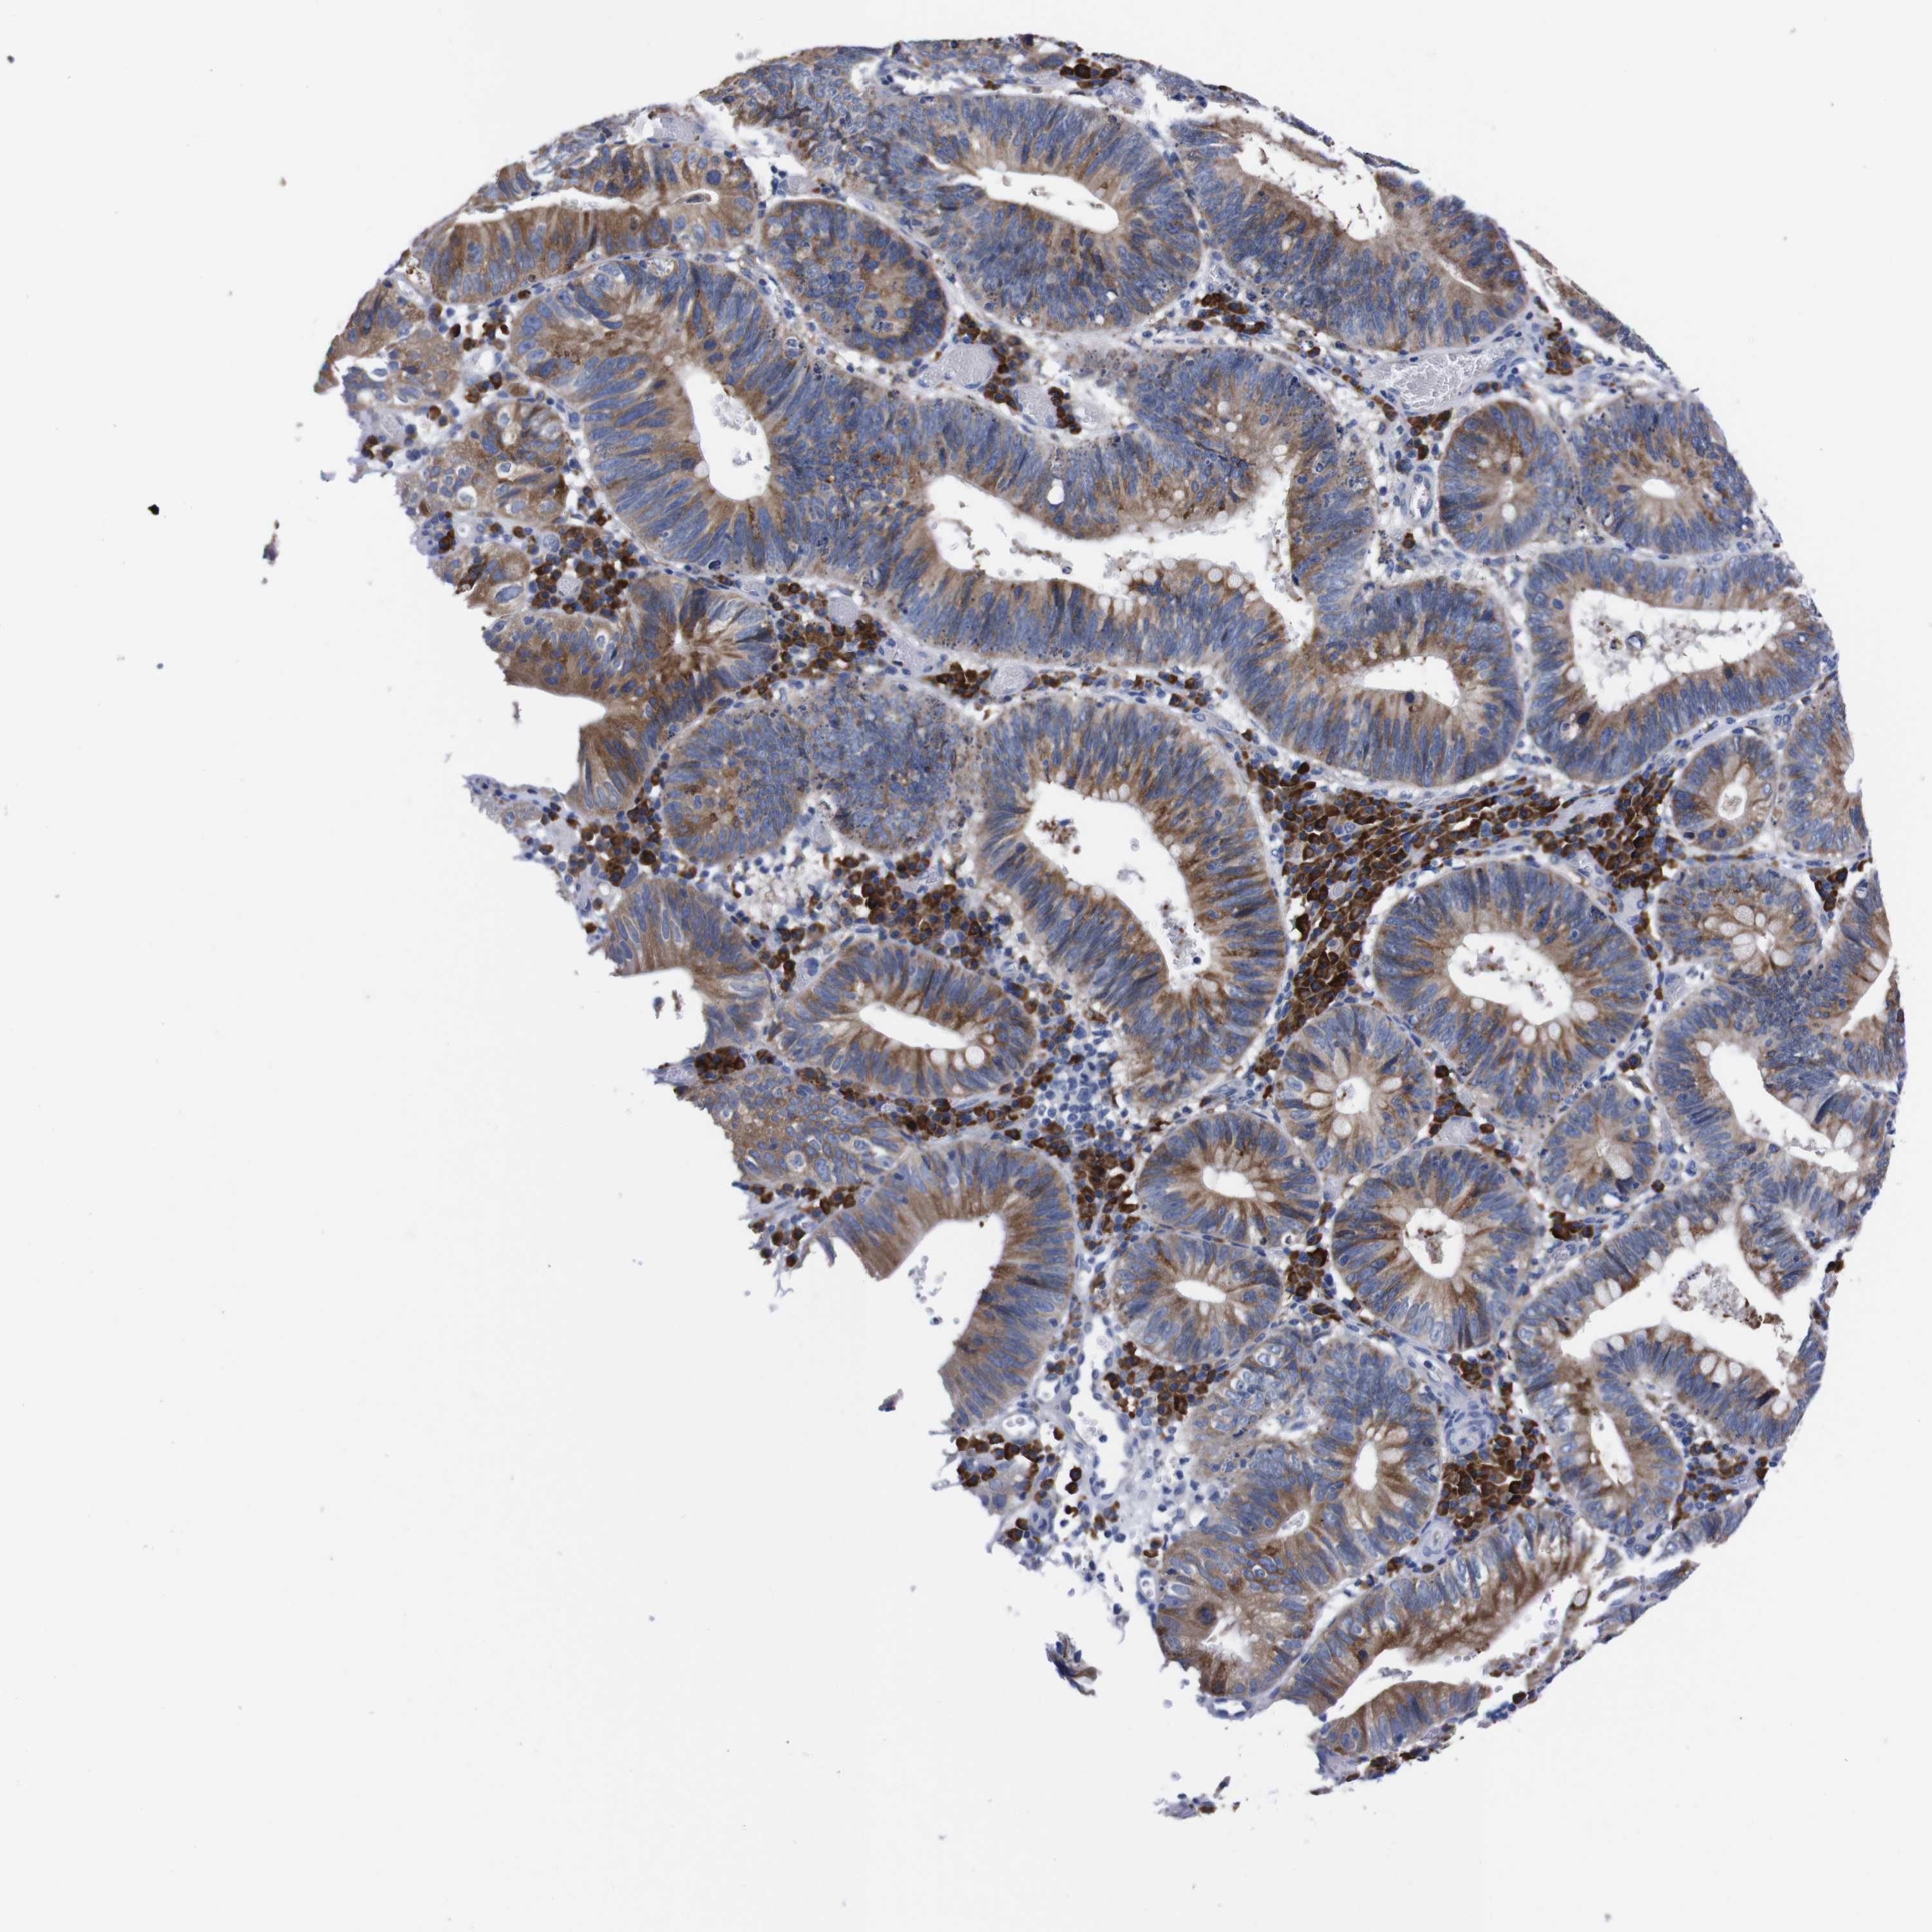

STOMACH CANCER - Protein expressioni

A mouse-over function shows sample information and annotation data. Click on an image to view it in a full screen mode. Samples can be filtered based on level of antibody staining by selecting one or several of the following categories: high, medium, low and not detected. The assay and annotation is described here.

Note that samples used for immunohistochemistry by the Human Protein Atlas do not correspond to samples in the TCGA dataset.

Antibody stainingi

Antibody staining in the annotated cell types in the current human tissue is reported as not detected, low, medium, or high, based on conventional immunohistochemistry profiling in selected tissues. This score is based on the combination of the staining intensity and fraction of stained cells.

Each image is clickable and will lead to virtual microscopy that enables deeper exploration of all samples and also displays staining intensity scores, fraction scores and subcellular localization as well as patient and tissue information for each sample.

Antibody HPA013994

Antibody HPA013995

Staining

High

Medium

Low

Not detected

Intensity

Strong

Moderate

Weak

Negative

Quantity

>75%

75%-25%

<25%

None

Location

Nuclear

Cytoplasmic/membranous

Cytoplasmic/membranous,nuclear

Adenocarcinoma, NOS

Adenocarcinoma, High grade